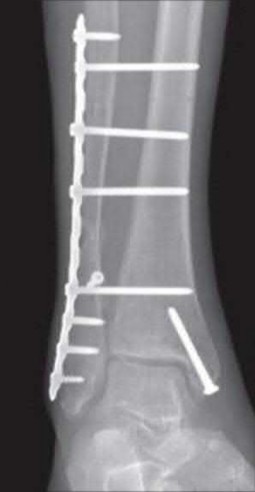

A 25-year-old female is involved in a motor vehicle collision. She presents with the isolated injury seen in Figures A through D. Her leg is swollen but her skin is intact. She has no clinical signs of compartment syndrome. Which of the following treatment options will allow for maintenance of fracture alignment and minimize the risk of soft tissue complications?

The patient presents with a closed distal third metaphyseal-diaphyseal distal tibia fracture with simple intra-articular extension. Immediate intramedullary nailing along with percutaneous fixation of the articular component provides appropriate restoration of length, rotation and alignment and minimizes the risk of wound complication.

Displaced distal third tibia fractures may be associated with simple intraarticular extension. Operative treatment of intra-articular distal tibia fractures has historically been performed with open reduction and internal fixation. Early open reduction and plate fixation of pilon fractures has been associated with high rates of infection and wound complication. In select patterns with simple articular extension, percutaneous screw fixation and medullary nailing may provide appropriate reduction with minimal soft-tissue risk.

Marcus et al. evaluated the outcomes of immediate intramedullary nailing and percutaneous fixation of simple intra-articular distal tibia fractures (AO/OTA 43 C1 and C2). The authors found excellent rates of union and alignment, however caution against broad application of this technique until more rigorous randomized studies can be performed.

Sirkin et al. retrospectively evaluated the results of a staged approach to management of intra-articular distal tibia fractures with temporary bridging external fixation followed by open reduction and internal fixation (ORIF). The authors found decreased rates of wound complication and infection compared with prior studies.

Figures A and B demonstrate a distal third tibial shaft fracture with simple intra-articular extension. The axial and coronal CT cuts in Figures C and D further clarify the articular injury. Illustrations A and B demonstrate a comminuted distal third tibial fracture with simple intra-articular extension. Illustrations C and D are fluoroscopic images of the same injury after intramedullary nailing and percutaneous fixation of the articular component.